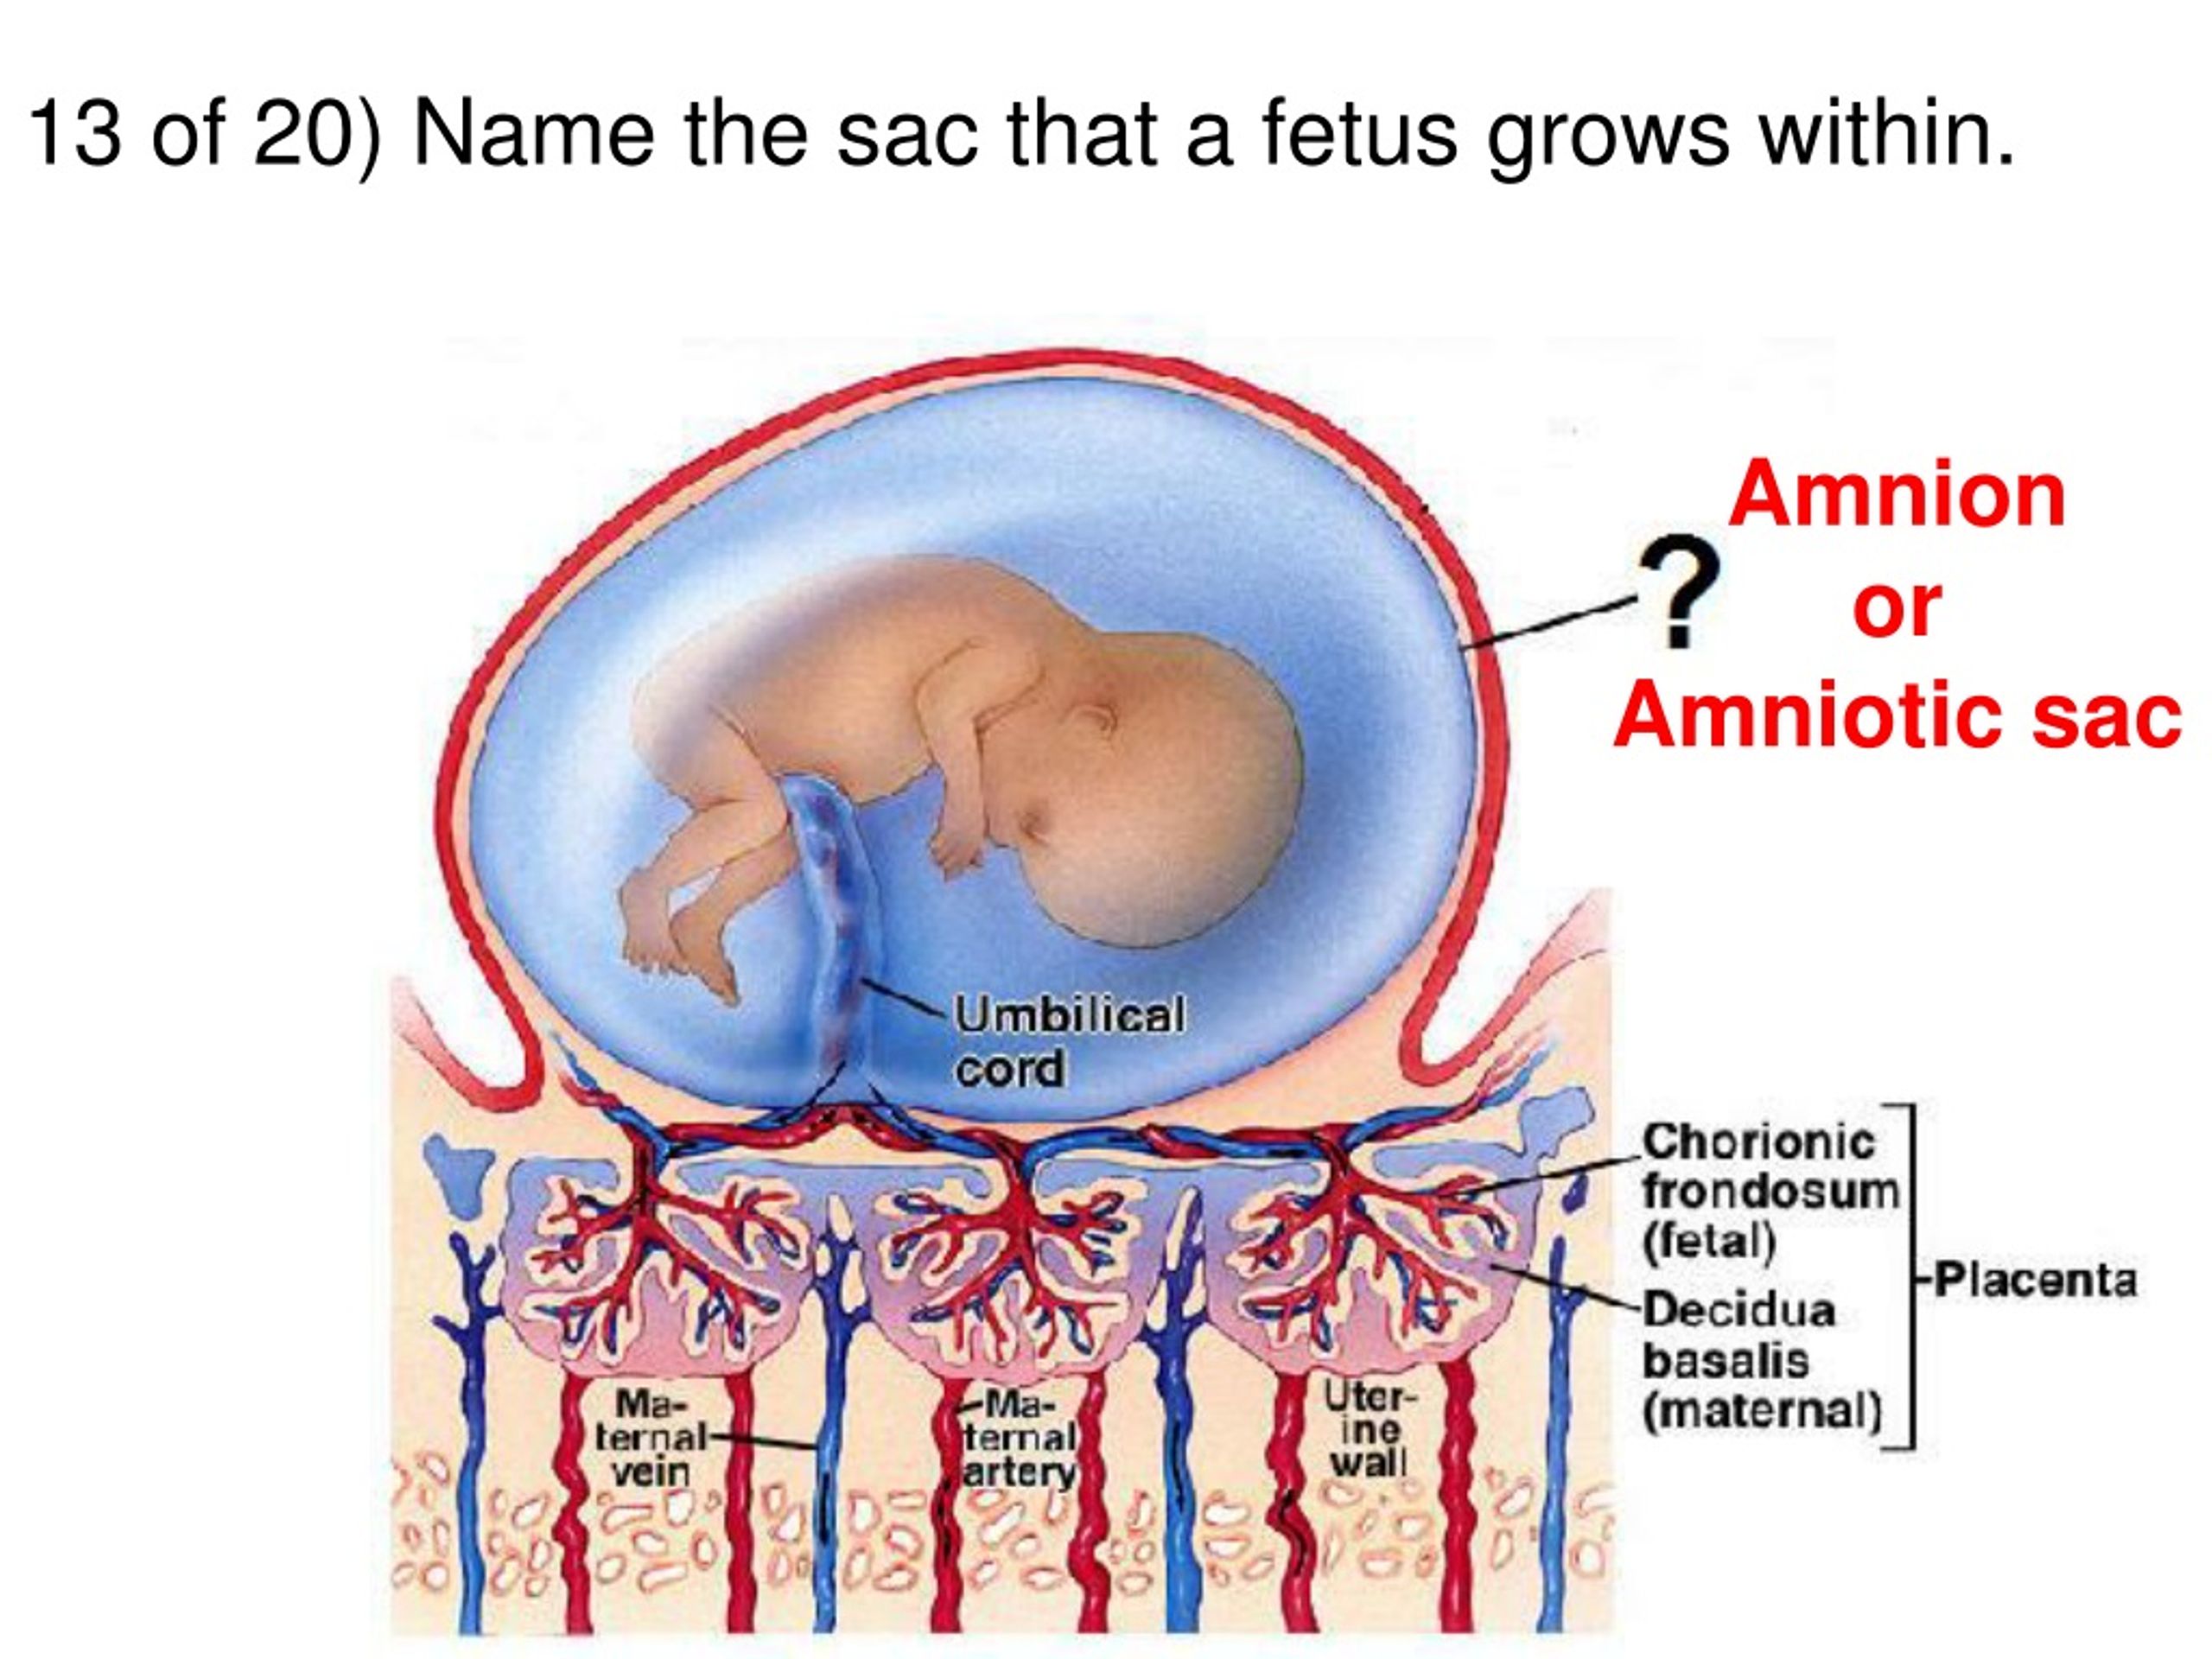

Околоплодный пузырь и плацента: структура и функции